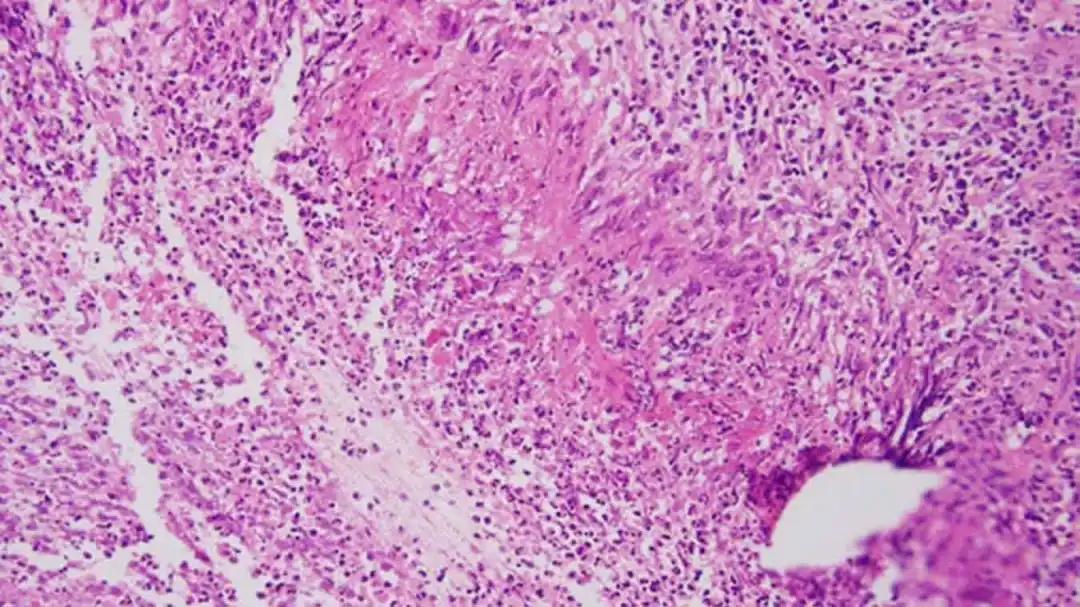

银屑病(Psoriasis)又称牛皮癣,是一种常见的慢性自身免疫性炎症皮肤病,不仅存在细胞组织不可逆损伤和免疫异常,还存在表皮干细胞的严重异常,患者皮肤上出现发炎的鳞状皮肤增生,会带来严重瘙痒和刺痛。

银屑病的病因与发病机制非常复杂。在遗传因素的基础上,各种环境因素诱导机体的神经内分泌系统异常,对皮肤中各种免疫细胞的调控失常,导致炎症性细胞因子的释放,进一步使机体的先天性与获得性免疫功能发生障碍,更多的炎症性细胞因子释放,引诱相关炎症细胞浸润,这种神经内分泌免疫炎症网络的逐级放大最终导致了银屑病特有的慢性炎症过程的形成与维持。